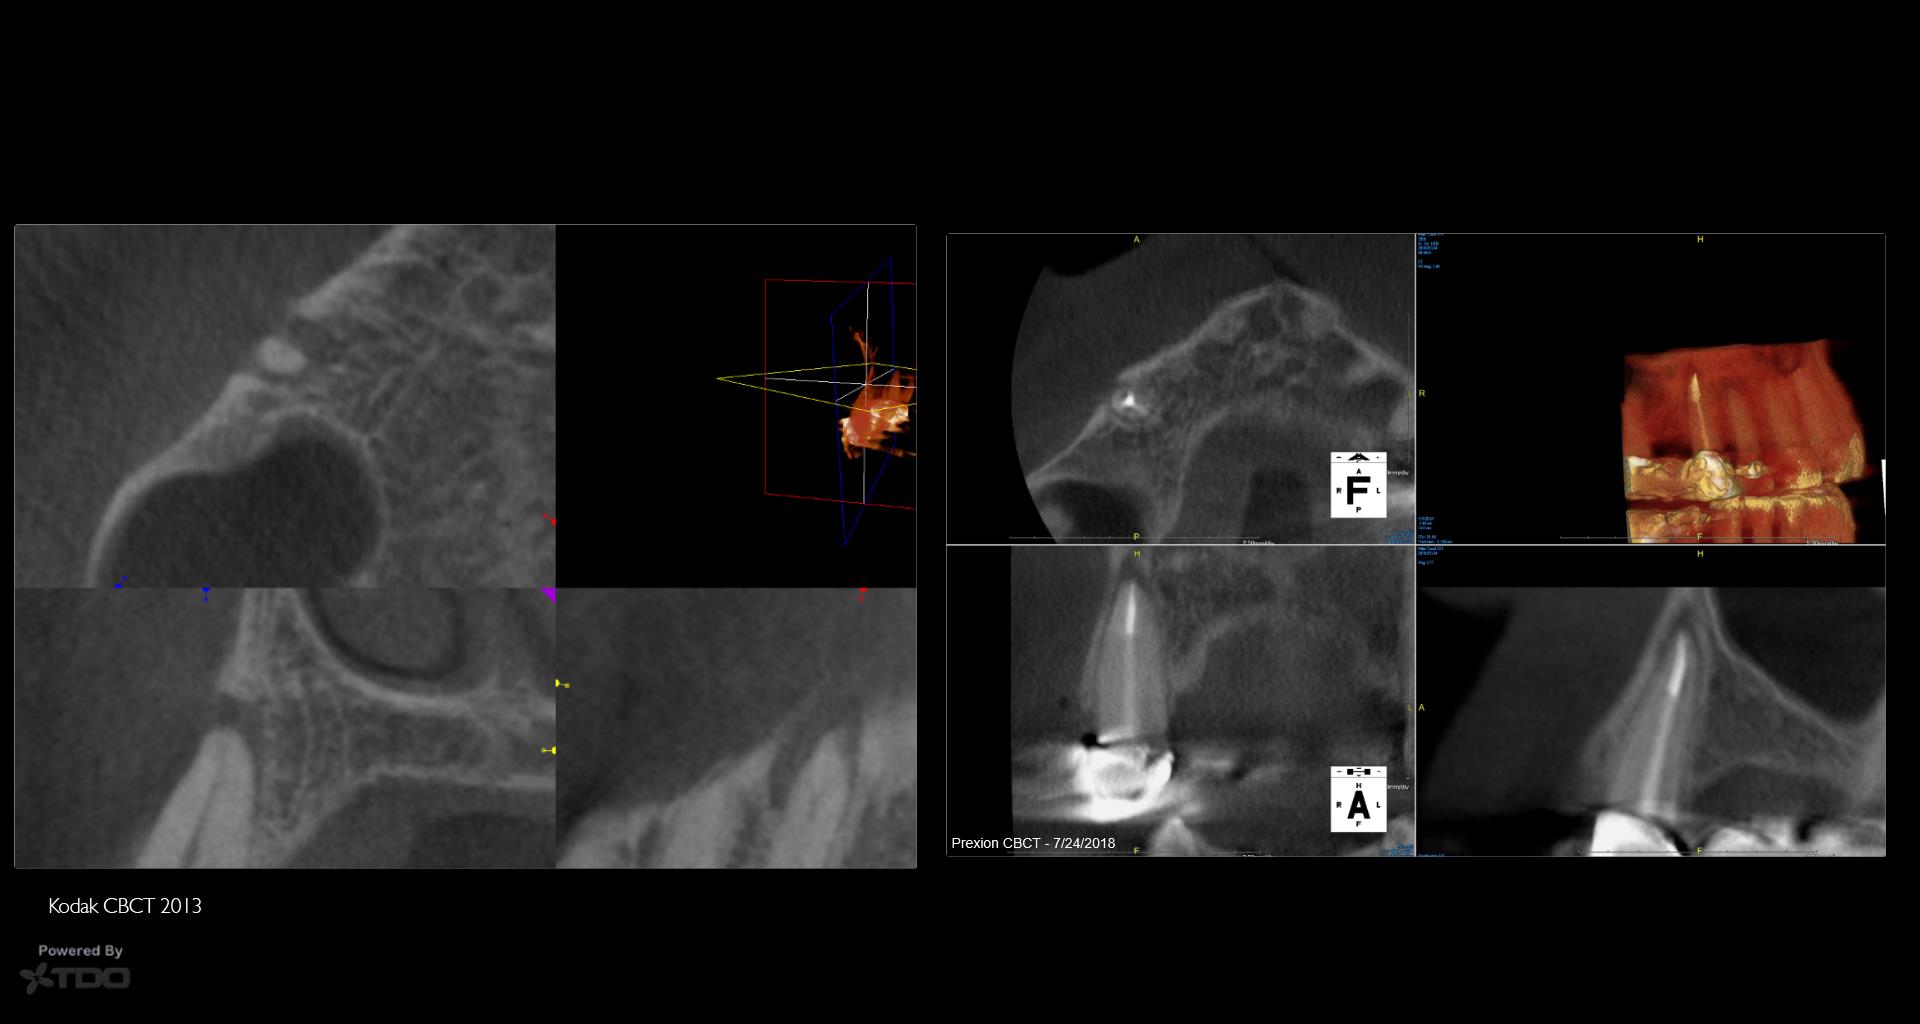

5 yr CBCT recall

Entire buccal plate missing. CBCT at 5 years suggests most, but not all, bone has regenerated. As canine bridge abutment, it is subjected to some occlusal trauma. gbc